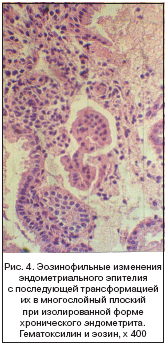

Характерной особенностью хронического эндометрита у пациенток менопаузального возраста являлось постоянное развитие плоскоклеточной метаплазии покровного, а в части случаев и железистого эпителия эндометрия (рис. 1, 2). Реже обнаруживалась муцинозная (эндоцервикальная) метаплазия. В связи с метапластическими процессами развивающиеся изменения эпителия имели характер преимущественно поверхностно–синцитиального и эозинофильноклеточного типов (рис. 3, 4), реже встречались светлоклеточный, реснитчатоклеточный (трубный) и «гвоздиковый» типы. В единичных случаях наблюдалась моруляция. Все типы метапластических изменений маточного эпителия могли симулировать рак эндометрия. При ассоциированной форме хронического эндометрита метаплазия и связанные с нею изменения эпителия вышеупомянутых типов встречались значительно чаще и имели более распространенный характер.